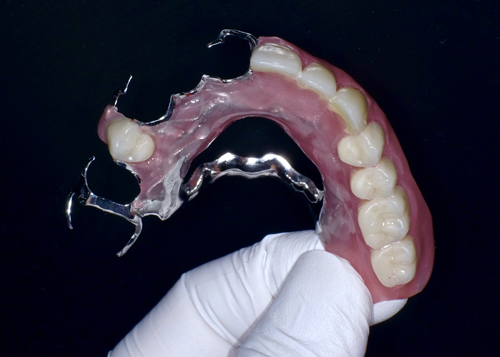

前歯をセレックを使用して全てキレイにやり変えました。

金具の見えない保険の入れ歯を用意しました。